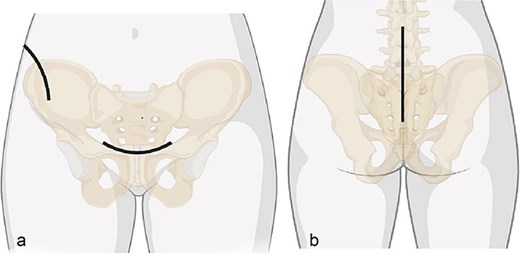

Surgical approaches diagram: (a) anterior approach; (b) posterior approach.

After one week of monitoring in the ICU, where she remained stable without need for ventilatory support, the patient was transferred to the ward. She then underwent the first surgical stage in supine position. Anterior pelvic fixation (Fig. 3a) was performed via a Pfannenstiel anterior approach combined with the first window of the right ilioinguinal approach, using a 3.5-mm reconstruction plate on the right anterior column crossing the pubic symphysis and a 3.5-mm retrograde screw in the left anterior column, inserted through the same Pfannenstiel access. During the same procedure, a 7.3-mm trans-sacral screw was placed in S1 on the right to stabilize the sacral fracture (Fig. 4). The surgery lasted ⁓3 h, and the patient was transferred to the semi-intensive care unit for postoperative monitoring.

The second surgical stage was performed under general anesthesia two weeks later, delayed by one week of hemodynamic monitoring and subsequent unavailability of surgical materials. In supine position, the left sacroiliac joint was fixed with two 7.3-mm cannulated screws, and a seroma in the Pfannenstiel approach was drained. Subsequently, with the patient repositioned in prone position (Fig. 3b), lumbopelvic fixation from L4-L5-S1 to the posterior ilium (EIPS) was performed using rods and pedicle screws (Fig. 5). This procedure lasted ⁓3 h. At this point, ˃3 weeks post-trauma, anatomical reduction was significantly hindered by early consolidation and fibrosis at the fracture sites, requiring extensive maneuvers. The patient was transferred to the ICU, extubated without complications the following day, and returned to the ward after two days, receiving hospital discharge thereafter.

The two-stage approach addressed initial severity (Fig. 3), using a Pfannenstiel and ilioinguinal approach for anterior fixation and an S1 trans-sacral screw for sacral stability [10, 11], followed by lumbopelvic fixation for posterior stability [12]. A 3-week delay, partly due to material unavailability, caused fibrosis, complicating reduction [13]. Seroma drainage in the second stage mitigated infection risks from the Pfannenstiel approach. ICU monitoring reflected management complexity despite stability [14]. Follow-ups over 18 months demonstrated functional recovery, quality-of-life gains, and psychological stability by 6 months, sustained to 18 months (Table 2, Fig. 7), despite early anxiety; this contrasts with studies linking severe psychological distress to poorer outcomes in Tile C fractures, suggesting early intervention mitigated these risks [5]. The Majeed score’s specificity, despite lacking a Portuguese version, and SF-12 supported outcomes analysis [15]. Pain assessment via the Numeric Pain Scale (NPS) revealed persistent lumbar pain radiating to right lower limb until the 4th week (NPS 4), resolving significantly by 3 months (NPS 1) and absent thereafter (Table 2, Fig. 7), consistent with rehabilitation progress and lumbopelvic fixation stability. This case underscores surgical timing challenges, the impact of delayed fixation, and multidisciplinary care’s value.